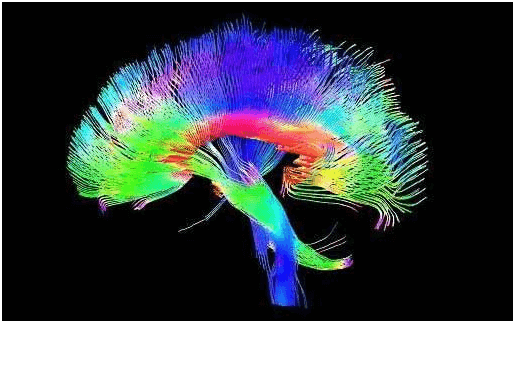

Diffusion tensor imaging (DTI) tractograpy. The color-coding of

Diffusion Tensor Imaging (DTI) - Fiber Tracking - Imagilys

Diffusion Tensor Imaging (DTI) - Fiber Tracking - Imagilys

Diffusion Tensor Imaging (DTI) revealing connectivity in the brain

Using Diffusion Tensor Imaging (DTI), axonal fiber tractography

A) Diffusion tensor imaging (DTI)-based whole-brain tractogram in